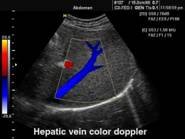

В Центре современных медицинских технологий «АКВА МЕД МАРИН» проводится УЗИ-диагностика на новейших ультразвуковых диагностических сканерах Экспертного класса SonoScape S40Exp и Премиум класса Toshiba SSA-780A, в том числе и УЗИ детям с применением специальных детских датчиков. Цветной допплер помогает точной диагностике патологии сосудов и сердца у взрослых и детей.

Компания SonoScape уделила особое внимание допплеровским режимам и является экспертом в своем классе, что позволяет с легкостью, но в то же время с уникальной точностью проводить исследования с постановкой наиболее точного диагноза.